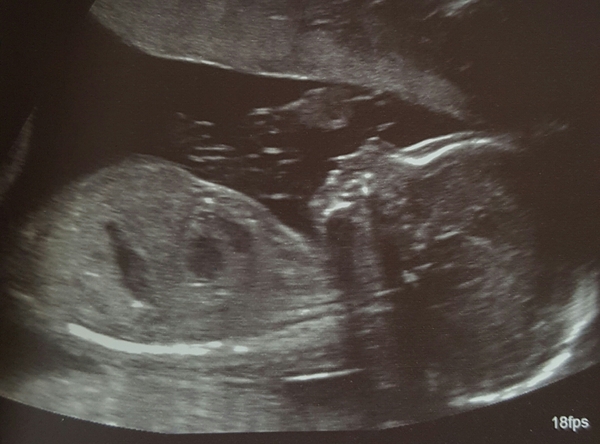

Hi ladies so sorry am shattered and not feeling great today. 20 week scan was amazing and baby fine. Hopefully cheer up those of you struggling with a pic. So sorry to hear about poo problems and echo calls to take care with dehydration. Will come back and try for personal messages later.

Lovely photo ickle 😊 xx

Ickle the picture is gorgeous, I can't wait to have my first (early) scan next week, at the moment I don't feel pregnant, just feel like I've got a nasty bug.

icklekid What a lovely scan photo. Thanks for posting it.

Ickle congrats on the scan. It's lovely.

Ickle Love the scan photo. Like reebok said, sometimes it'd hard to remember that you are growing a baby and not just I'll. I had a scan yesterday and we could see a full head of hair, it was weird.

Ickle, lovely scan photo from Monday.

ickle lush scan, hope ds was up a more sensible time today! Mine is an early riser too!